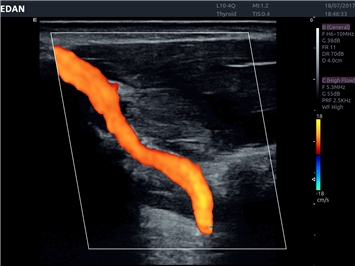

EDAN Acclarix LX4 представляет собой инновационную ультразвуковую систему, построенную на усовершенствованной платформе Acclarix. Сочетание высокого качества визуализации с интеллектуальным рабочим процессом делает эту систему оптимальным выбором для клиник, ценящих эффективность и экономичность.

• Сосудистой диагностики

Направленный энергетический допплер:

Да

Энергетический допплер:

Цветовой допплер: